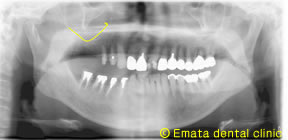

Before

患者さんは、右上奥歯をインプラント治療を希望されて来院された62才の男性の方です。上顎洞底の位置が低く、CT撮影で外側の骨も喪失してることがわかりました。奥歯の上には上顎洞という空洞(黄色の矢印の線)がありこのままではインプラントが上顎洞内に突き抜けてしまうためインプラントの手術ができません。